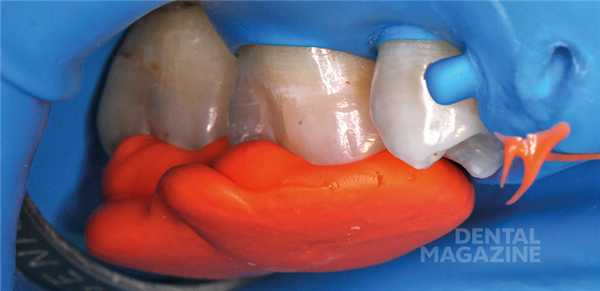

После изоляции рабочего поля (рис. 2) и механической отчистки от налета с поверхности зубов снимается ключ bite-силиконом с учетом габаритов клампа (рис. 3) .